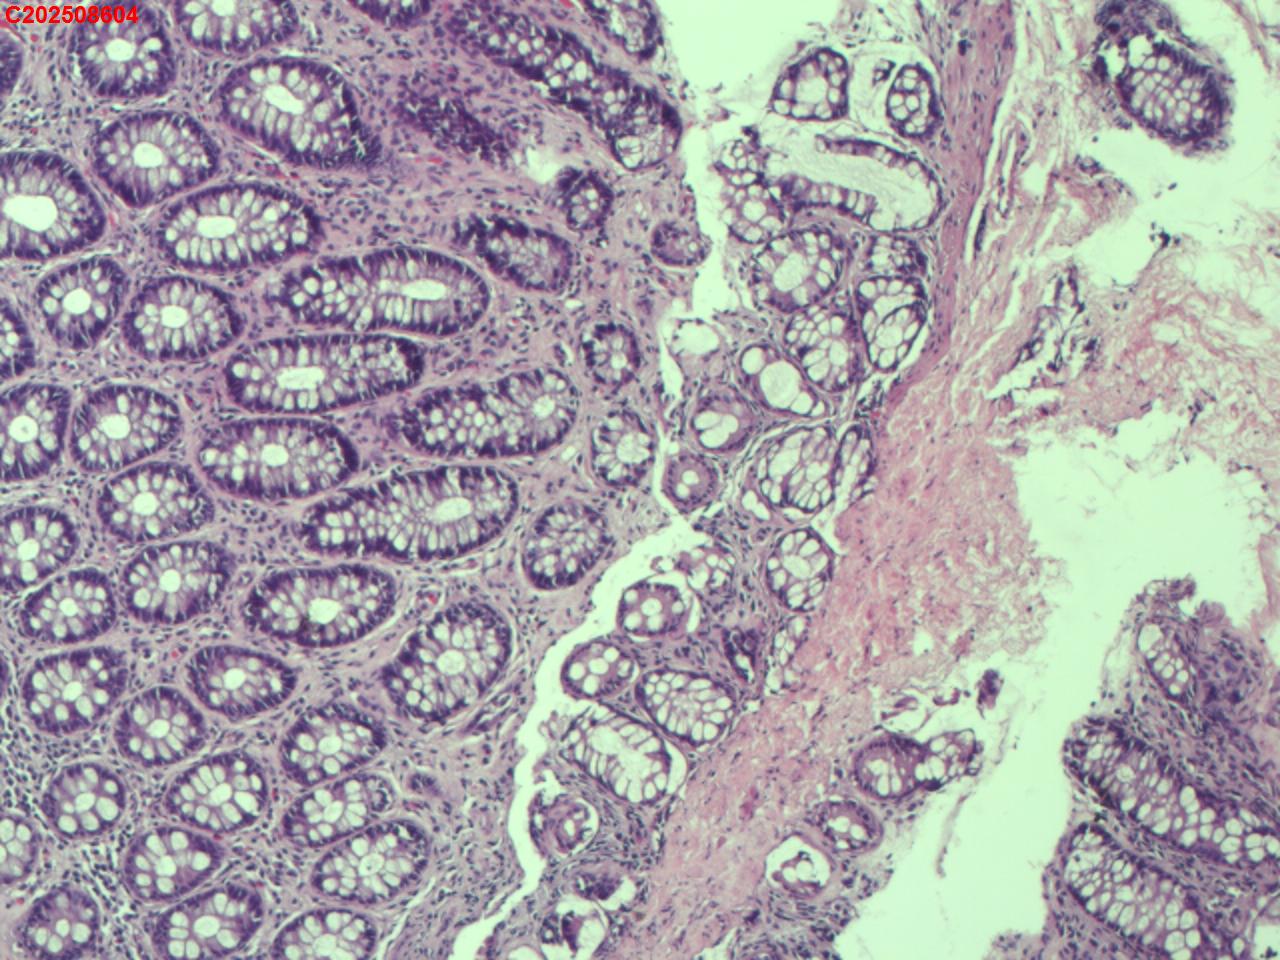

直肠粘膜

女

65岁

直肠息肉

腹部不适

直肠可见多发直径2mm息肉。

大肠粘膜增生性息肉。